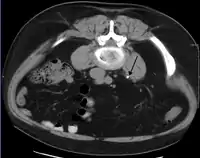

وإلا فإن التصوير بالحزمة الإسطوانية الحلزونية الطبقي المبرمج بمقاطع 5 مليمتر (0.2 بوصة) هو الطريقة التشخيصية الأفضل في التقييم الشعاعي لتحصي الكلية المشتبه به.[3][13][43][46][47] يمكن الكشف عن جميع الحصوات بالأشعة المقطعية باستثناء نوع من الحصوات النادرة جدًا، التي تتكون من بعض بقايا الأدوية الموجودة في البول،[48] مثل إندينافير. الحصوات التي تحتوي على الكالسيوم تكون ظليلة للأشعة نسبيًا، ويمكن الكشف عنها في كثير من الأحيان عن طريق التصوير الشعاعي التقليدي للبطن، الذي يشمل الكلى، والحالب، والمثانة.[48] حوالي 60٪ من جميع الحصوات الكلوية تكون ذات كثافة إشعاعية عالية.[46][49] وبشكل عام، فإن حصوات فوسفات الكالسيوم لديها أكبر كثافة، تليها أكسالات الكالسيوم، وحصوات فوسفات الأمونيوم والمغنيسيوم. بينما حصوات السيستين هي فقط التي تكون ضعيفة الكثافة الإشعاعية، في حين أن حصوات حمض اليوريك عادة ما تكون شفافة تمامًا إشعاعياً.[50]